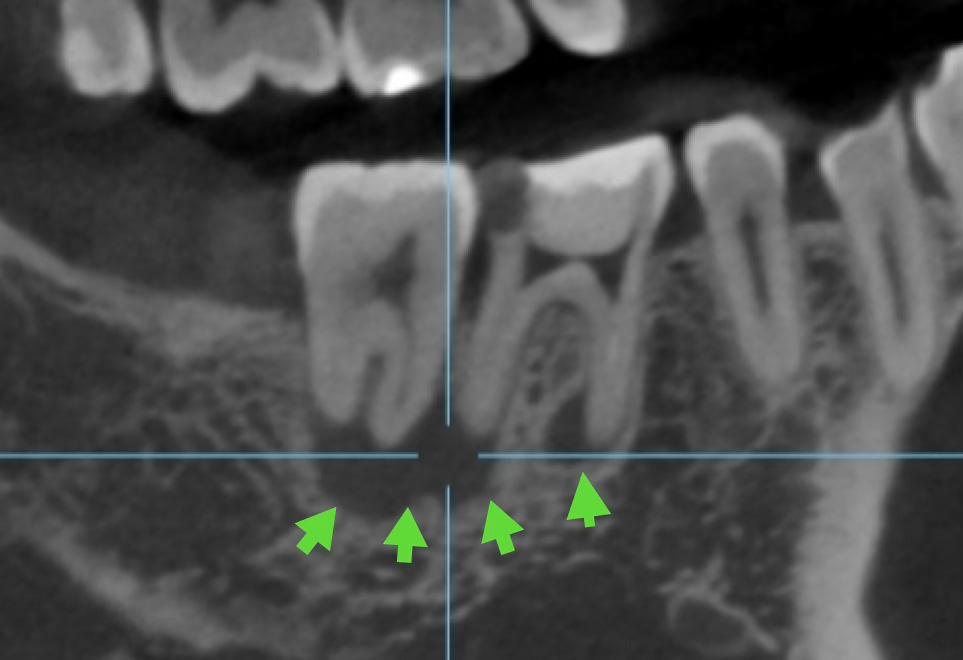

初めの治療から早くも2年以上が経過しました。その経過を確認するためにCTを撮影しました。初診時の矢印部分を見ていただければおわかりいただけると思いますが、透過像がなくなり、骨がしっかりと再生して治っているのがわかります。